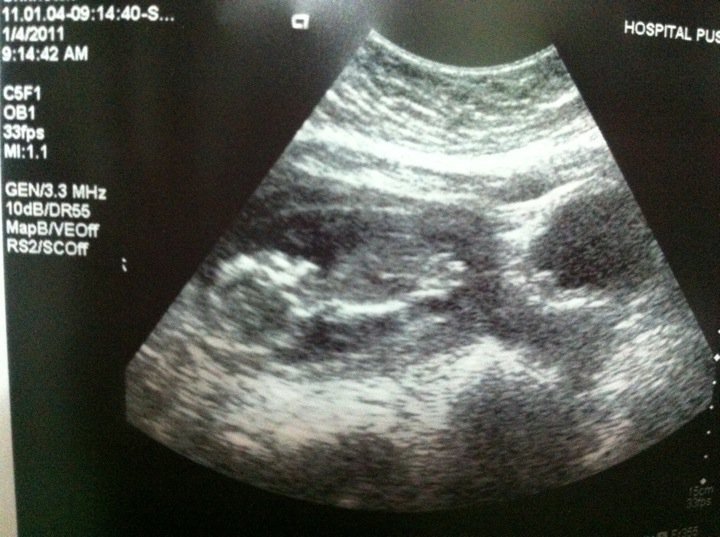

My baby at 14-15 weeks with fibroid underneath her/him =) |